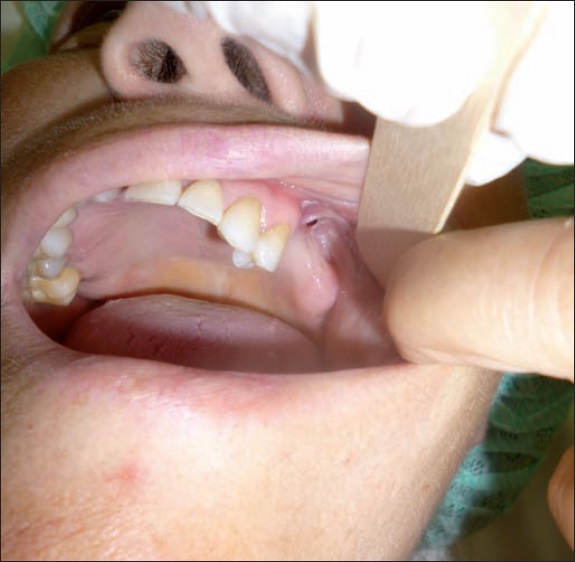

Al examen clínico observamos un defecto en el reborde alveolar de 3 mm de diámetro ( Fig. 1), confirmado en exámenes radiológicos (ortopantomografía y tomografía axial computarizada), con opacificación del seno maxilar y comunicación oroantral izaquierda, además de hipodensidad del cuerpo mandibular derecho ( Fig. 2). Establecimos así el diagnóstico de osteonecrosis por bifosfonatos de la hemimándibula derecha y del maxilar izquierdo, con fístula localizada a nivel del diente 26.